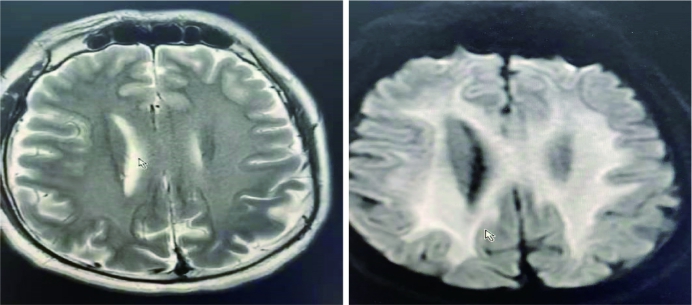

2.2 实验室检查患者A:毒物监测阴性,行心电图检查、心脏超声及头胸部CT均未见明显异常(见图 1A)。患者B:毒物监测血液氟乙酸乙酯浓度0.1 μg/mL,心肌酶升高(见图 2),尿素、肌酐升高提示急性肾损伤,心电图提示正常范围心电图,心脏超声:二尖瓣、三尖瓣关闭不全;胸部CT示:双肺炎症、少量胸腔积液(见图 1B);多次复查头颅CT未见明显异常。患者C:毒物监测阴性,心肌酶升高(见图 2),尿素、肌酐升高提示急性肾损伤,心电图提示正常范围心电图,心脏超声:三尖瓣关闭不全,左室收缩功能减低,左室室壁搏动节段性异常;冠脉血管造影未见明显异常;胸部CT示:双肺炎症,少量胸腔积液(见图 1C);多次复查头颅CT未见明显异常,发病第4天查头颅MRI:双侧小脑中脚、双侧基底节区/双侧脑室体旁及胼胝体对称异常新号,不排除中毒性脑病(见图 3),冠脉血管造影未见明显异常。

| A:T2加权像,B:T1加权像 图 3 患者C发病第4天头颅MRI |

本文3例患者均为接触氟乙酸乙酯后出现头晕、恶心、呕吐,其中2例重症患者,出现有循环系统和神经系统表现,经紧急抢救及后续ICU治疗恢复正常生活,与文献中氟乙酸类衍生物中毒报道的相一致[7, 9, 11, 14-15]。但本研究总结了3例患者的一些共性规律:(1)吸入性氟乙酸乙酯中毒患者严重程度与吸入剂量相关;本文患者A,发现刺激性气体后就远离污染源,整个病程均未出现室颤及中毒性脑病等表现;而其同伴患者B发现吸入刺激性气体后再次进入污染区工作后出现危及生命的室颤及中毒性脑病;而患者C在污染区打球后发病,吸入时间长,引起严重的循环和神经系统表现;与口服氟乙酸类衍生物报道一致[14]。(2)氟乙酸乙酯检测浓度与吸入剂量和检测时间相关[16],本文只有患者B检测到极高氟乙酸乙酯(接触36 h时抽血送检),血浆吸附加滤过后复检阴性(发病第5天);与患者B同时送检的患者A毒物分析阴性,考虑与患者A吸入剂量较少有关;患者C送检毒物分析阴性考虑抽血检测时间离发病时间太久有关(发病第7天)。(3)氟乙酸乙酯中毒患者均出现双侧肺炎及少量胸腔积液,这与常见有机氟气体中毒表现一致[1]。(4)患者心肌损伤过程与文献报道不一致[17],文献报道心肌酶在约3~4 d达最大值,1周开始下降,本研究病例显示发病第2天甚至第1天心肌酶即达到最大值,发病第4天基本恢复正常;同时笔者发现重症患者心脏超声均出现不同程度的二尖瓣/三尖瓣关闭不全,考虑与中毒后心肌缺血及炎症反应有关;3例患者出现症状后均迅速至当地县医院治疗,治疗过程中部分患者出现恶性心律失常,抢救治疗后目前随访均未遗留后遗症;与文献报道的有机氟气体或氟乙酸钠中毒病死率极高不符[4-5, 7],笔者认为患者致死的主要因素是出现恶性心律失常,发病后尽快到具备抢救条件的医疗机构就诊是抢救成功的关键,提示在类似工作场景下心肺复苏的全员培训可能改变该类患者的预后。(5)中毒性脑病患者预后良好,本文重症患者均出现不同程度的神经系统表现,2例重症患者均存在不同程度的休克,积极纠正休克的同时保证脑灌注压是中毒性脑病预后良好的关键,对比了有限的影像学资料发现氟乙酸乙酯中毒性脑病与文献报道的氟乙酰胺等中毒引起的脑病MRI表现一致:以胼胝体为中心的广泛白质病变,皮质不受损害[11]。